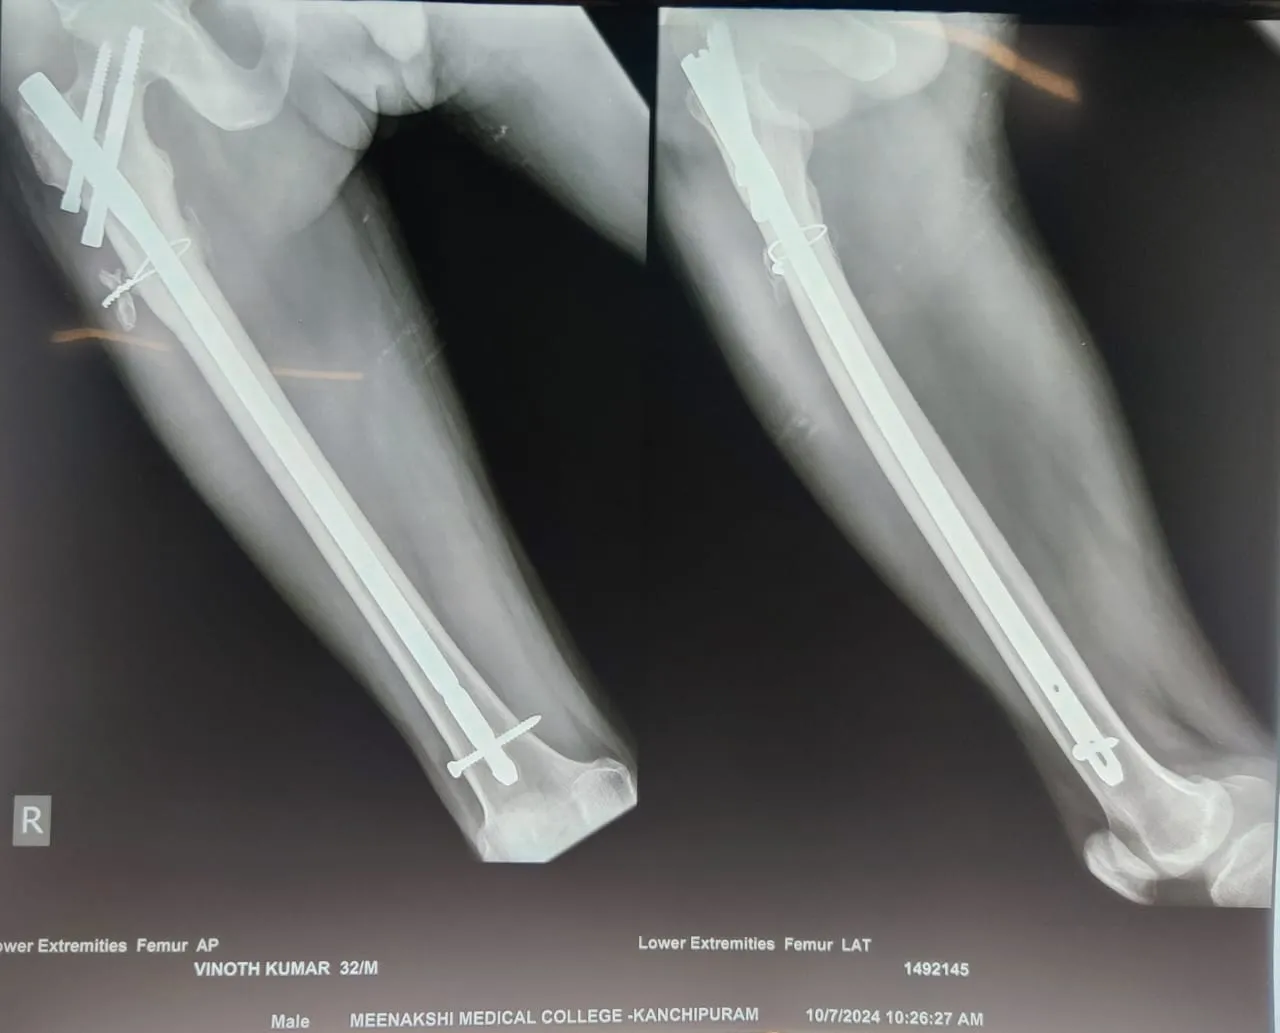

Quality and affordable healthcare has long been the essence in the field of medical sciences & treatment. Every patient expects an early diagnosis and a planned approach to treatment procedures with affordability and access to quality healthcare. Knee replacement, Hip replacement, Fracture treatment are being done by Dr.P.Sankaralingam at very affordable costs without compromising on quality.

Dr.P.Sankaralingam M.S(ortho)., DNB (ortho).,MNAMS is an experienced senior consultant Orthopaedic surgeon who does about 350 joint replacement surgeries per year in addition to treatment of Trauma cases.

Standard Hospital, Chennai’s Centre of Excellence for Orthopaedics offers minimally invasive surgeries for faster recovery.